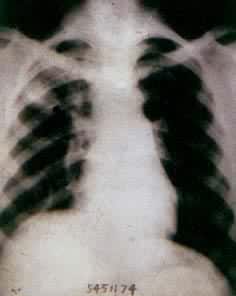

肺部疾病(一) 肺部疾病(二) 大叶肺炎 小叶肺炎 间质性肺炎 肺脓肿(正位) 肺脓肿(侧位) 支气管扩张 浸润性肺结核

肺结核空洞 肺不张